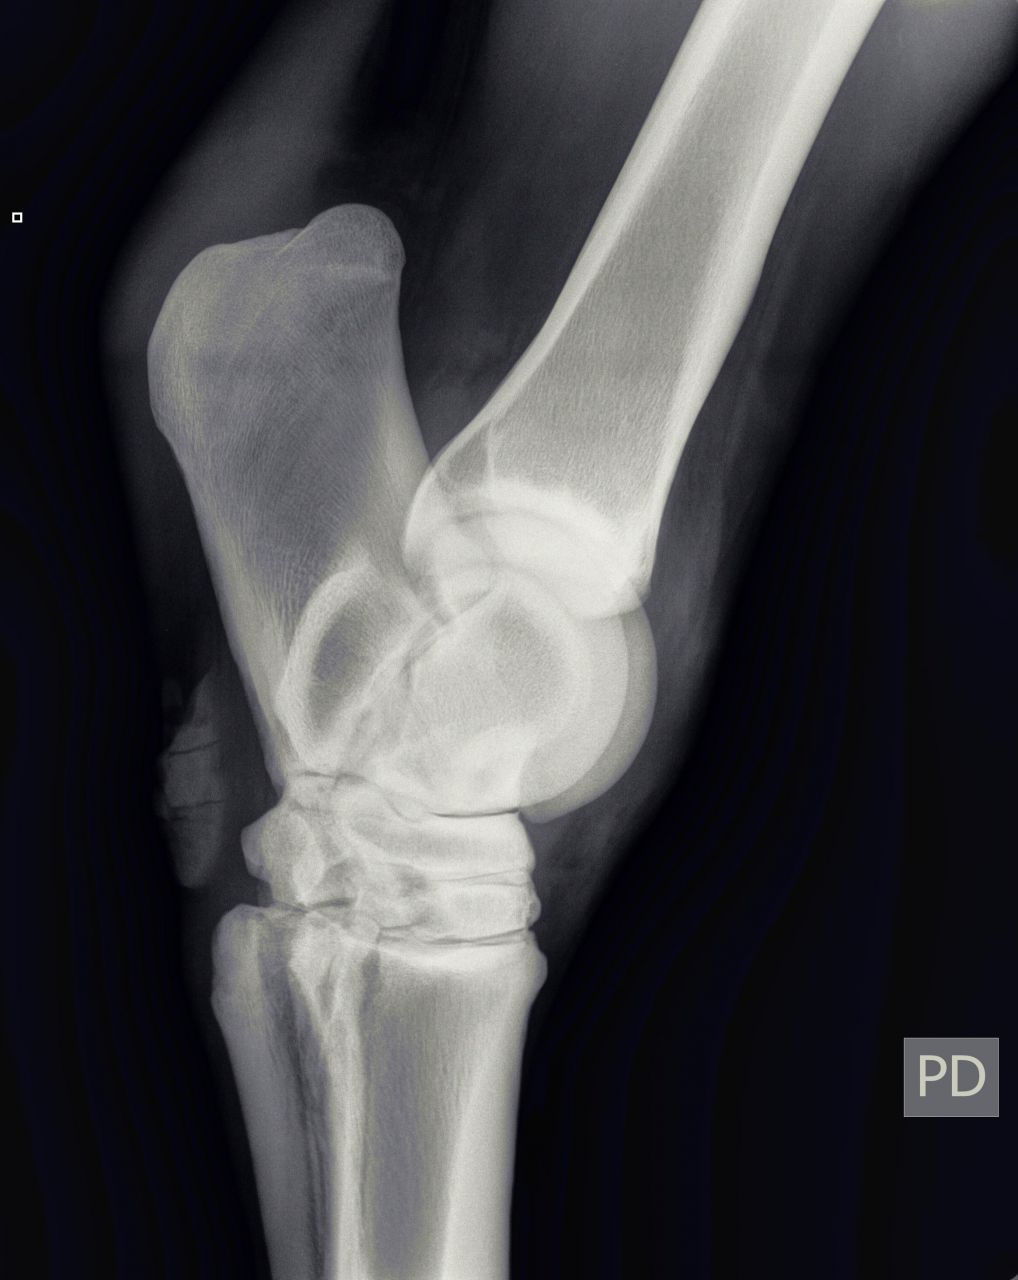

| Dire merci | Bonjour, le vétérinaire vient de diagnostiquer un début d'éparvin sur un des postérieurs de ma jument. Voici les radios : [url=https://www.1cheval.com/membre/services/photos/images/198166.jpg" class='zoombox zgallery3311504' ] ![]() [/url] [url=https://www.1cheval.com/membre/services/photos/images/198165.jpg" class='zoombox zgallery3311504' ] ![]() [/url] [url=https://www.1cheval.com/membre/services/photos/images/198164.jpg" class='zoombox zgallery3311504' ] ![]() [/url] il me propose comme soins : tildren en IV et ferrure avec plus d'éponge Que pensez-vous de ce traitement? je suis perdu quant à la marche à suivre (le traitement vaut 500€ et sans garanti de résultat même si le véto a bon espoir) Ceci dit, je viens de rencontré quelqu'un à qui ce même véto à déconseillé le tildren pour sa jument qui a un éparvin. Une amie en a parlé à son véto (spé équin aussi) qui lui a dit qu'on pouvait tenter aussi les ondes de choc. Je ne connais pas le prix Quelqu'un a-t-il déjà testé sur l'éparvin? Que faire d'autre? J'ai bien fait cure d'harpagophyt, sans amélioration. en voici plus sur ma jument : Celle-ci est une arabo-appalossa de 12 ans, née chez moi, débourrée à 5-6 ans et qui fait du loisir modéré. Elle s'est mise à boiter suite à une endurance (10 km) où il y avait un fort dénivelé en tout début et toute fin de (au point que je suis descendu d'elle pour descendre le chemin en crabe). La jument était largement entrainée avant (elle aurait pu courir une 20 voir une 40) elle est au repos depuis (ca fait 3 mois et demi) et j'ai l'impression que la boiterie s'aggrave un peu (c'est intermittent) lorsque je l'ai emmener au vétérinaire, elle ne boitait pas, les tests de flexions ont ré-déclenché la boiterie. La jument est ferrée en rolls des 4 pieds depuis 6 mois (et plus d'un an des antérieurs) |